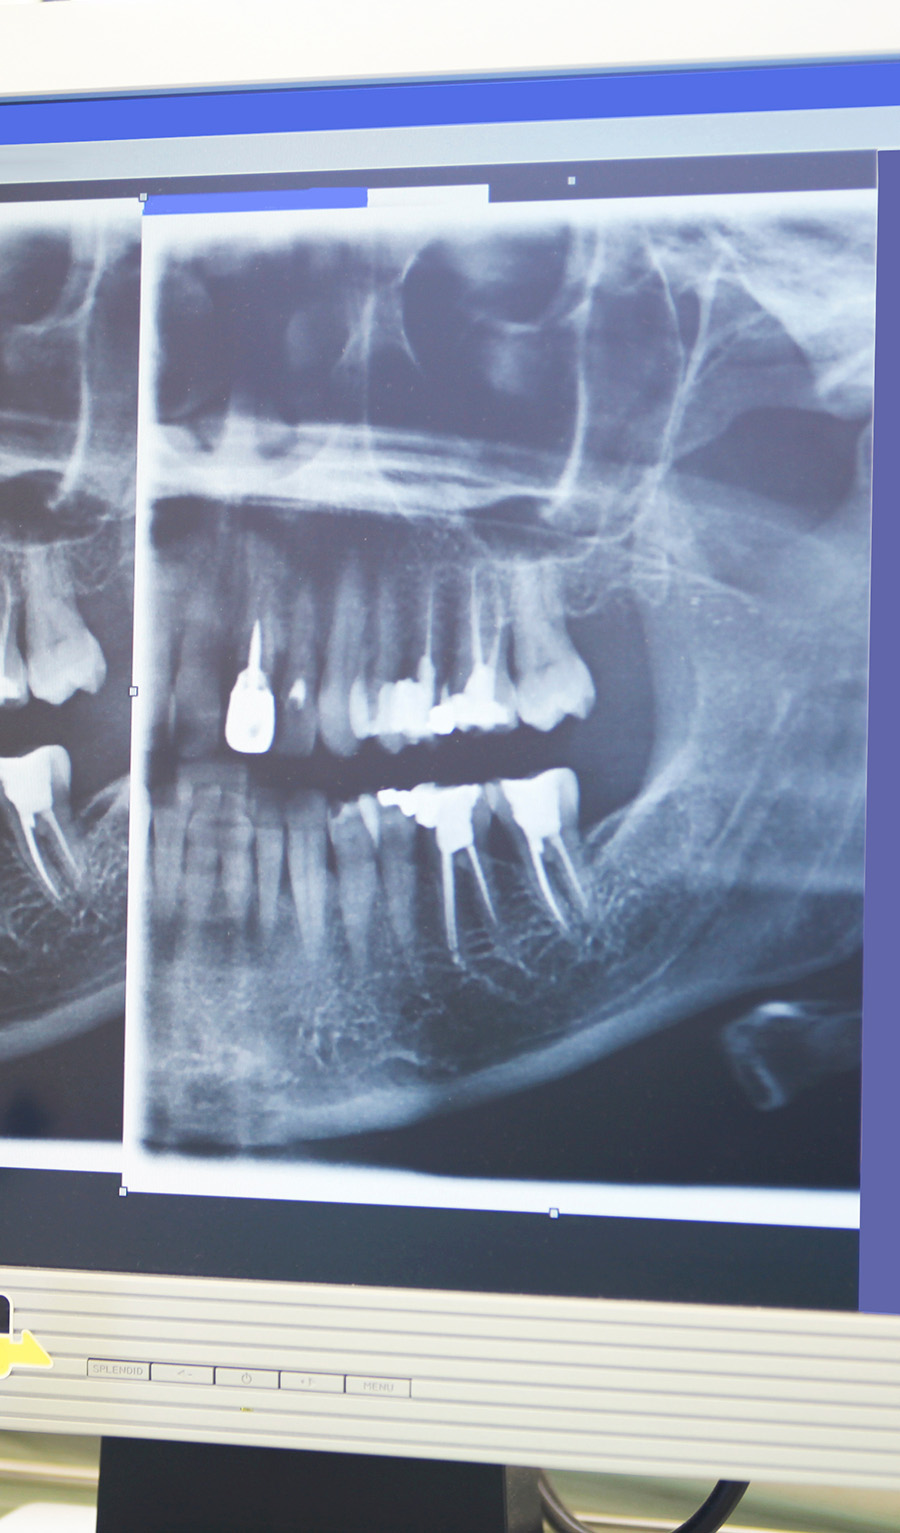

X-ray

To find the source of your dental pain, your dentist will begin by performing a comprehensive exam and review of your x-rays to get a complete picture of your oral health. If your tooth is infected, they will determine the extent of the infection to decide if root canal therapy will be an effective treatment. If you end up needing a root canal, your dentist will begin the therapy by numbing the treatment site, all the way down to the nerves. Your dentist will discuss sedation options with you before starting the procedure.